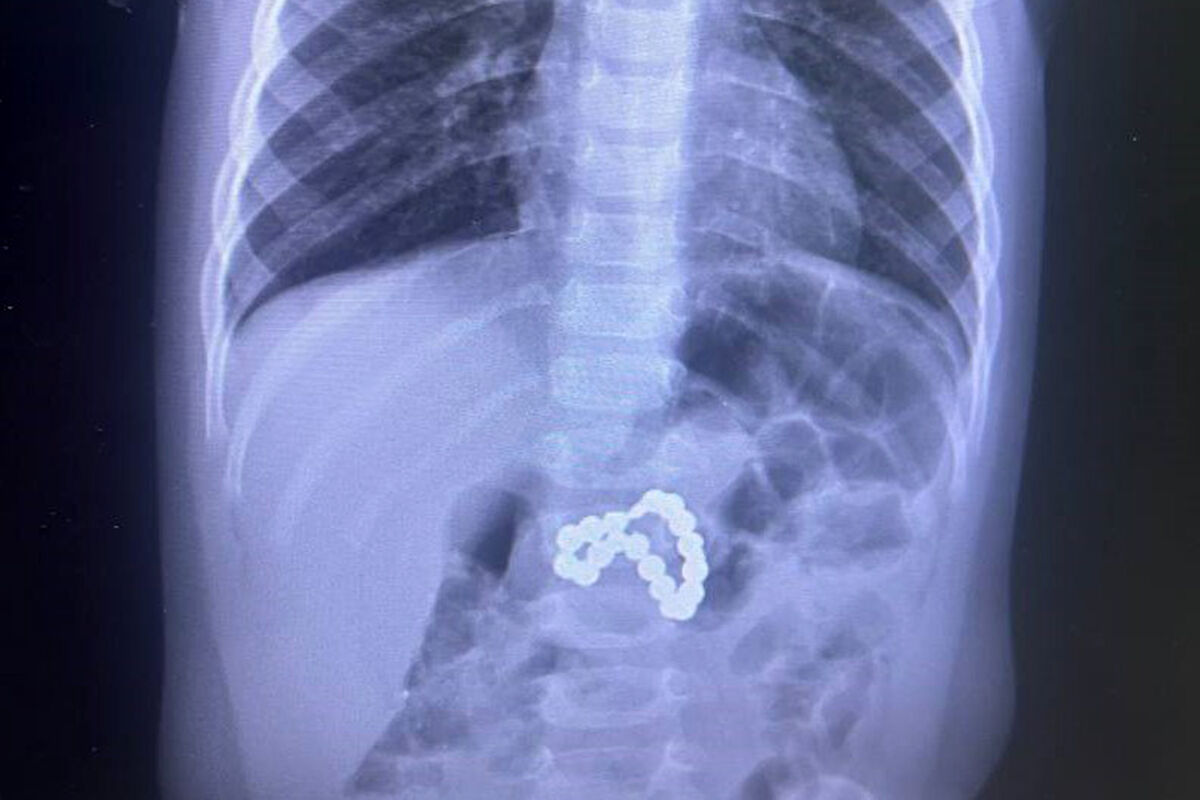

Врачи Центра охраны материнства и детства Сургута спасли девочку, которая поступила в больницу в тяжелом состоянии, проглотив магниты от браслета. Об этом в Telegram-канале сообщила руководитель центра Лариса Белоцерковцева.

Ребенок проглотил несколько магнитных шариков от детского браслета, в больницу ее доставили в тяжелом состоянии. Было принято решение о проведении экстренного хирургического вмешательства, инородные тела вызвали перфорацию кишечника и желудка.

До этого сообщалось, что хирурги городской детской клинической больницы Омска спасли двухлетнего мальчика, который проглотил 70 магнитных шариков от игрушки. Операция длилась более четырех часов, магниты успели притянуться друг к другу в плотное кольцо, произошла перфорация кишечника. Хирургам удалось извлечь все 70 шариков.